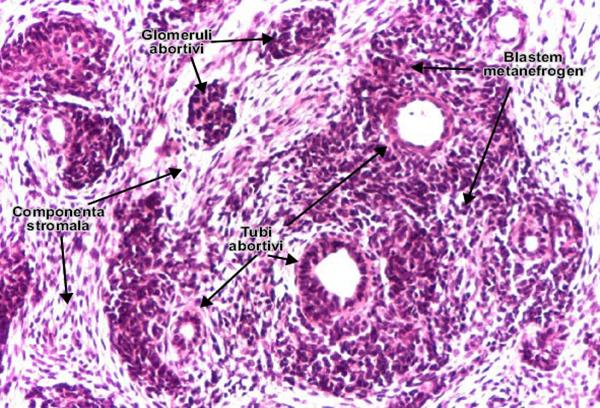

Nefroblastomul este constituit din trei componente, dezvoltandu-se din blastemul metanefrogen si

derivatele sale stromale si epiteliale.

Componenta epiteliala, majoritara, este reprezentata de tubi si glomeruli abortivi, nefunctionali. Rar, mai pot exista si alte tipuri de epitelii: scuamos sau mucinos. Componenta stromala (mezenchimala) are aspect sarcomatos, fiind constituita din celule cu caracter fibrocitar, mixoid, de muschi neted/striat, tesut adipos, osteoid, condroid, neurogenic. Blastemul este format din plaje de celule mici, hipercromatice, cu tablou difuz. Tumora este bogat vascularizata si comprima parenchimul renal normal invecinat.[21]

Figura 9.6. Nefroblastomul (tumora Wilms). Cele trei componente ale tumorii : blastemul metanefrogen, componenta mezenchimala si cea epiteliala. (Hematoxilina-eozina, ob. x20). Adaptat dupa M. Danciu, M-S Mihailovici, Atlas de morfopatologie, 2004, www.pathologyaltas.ro